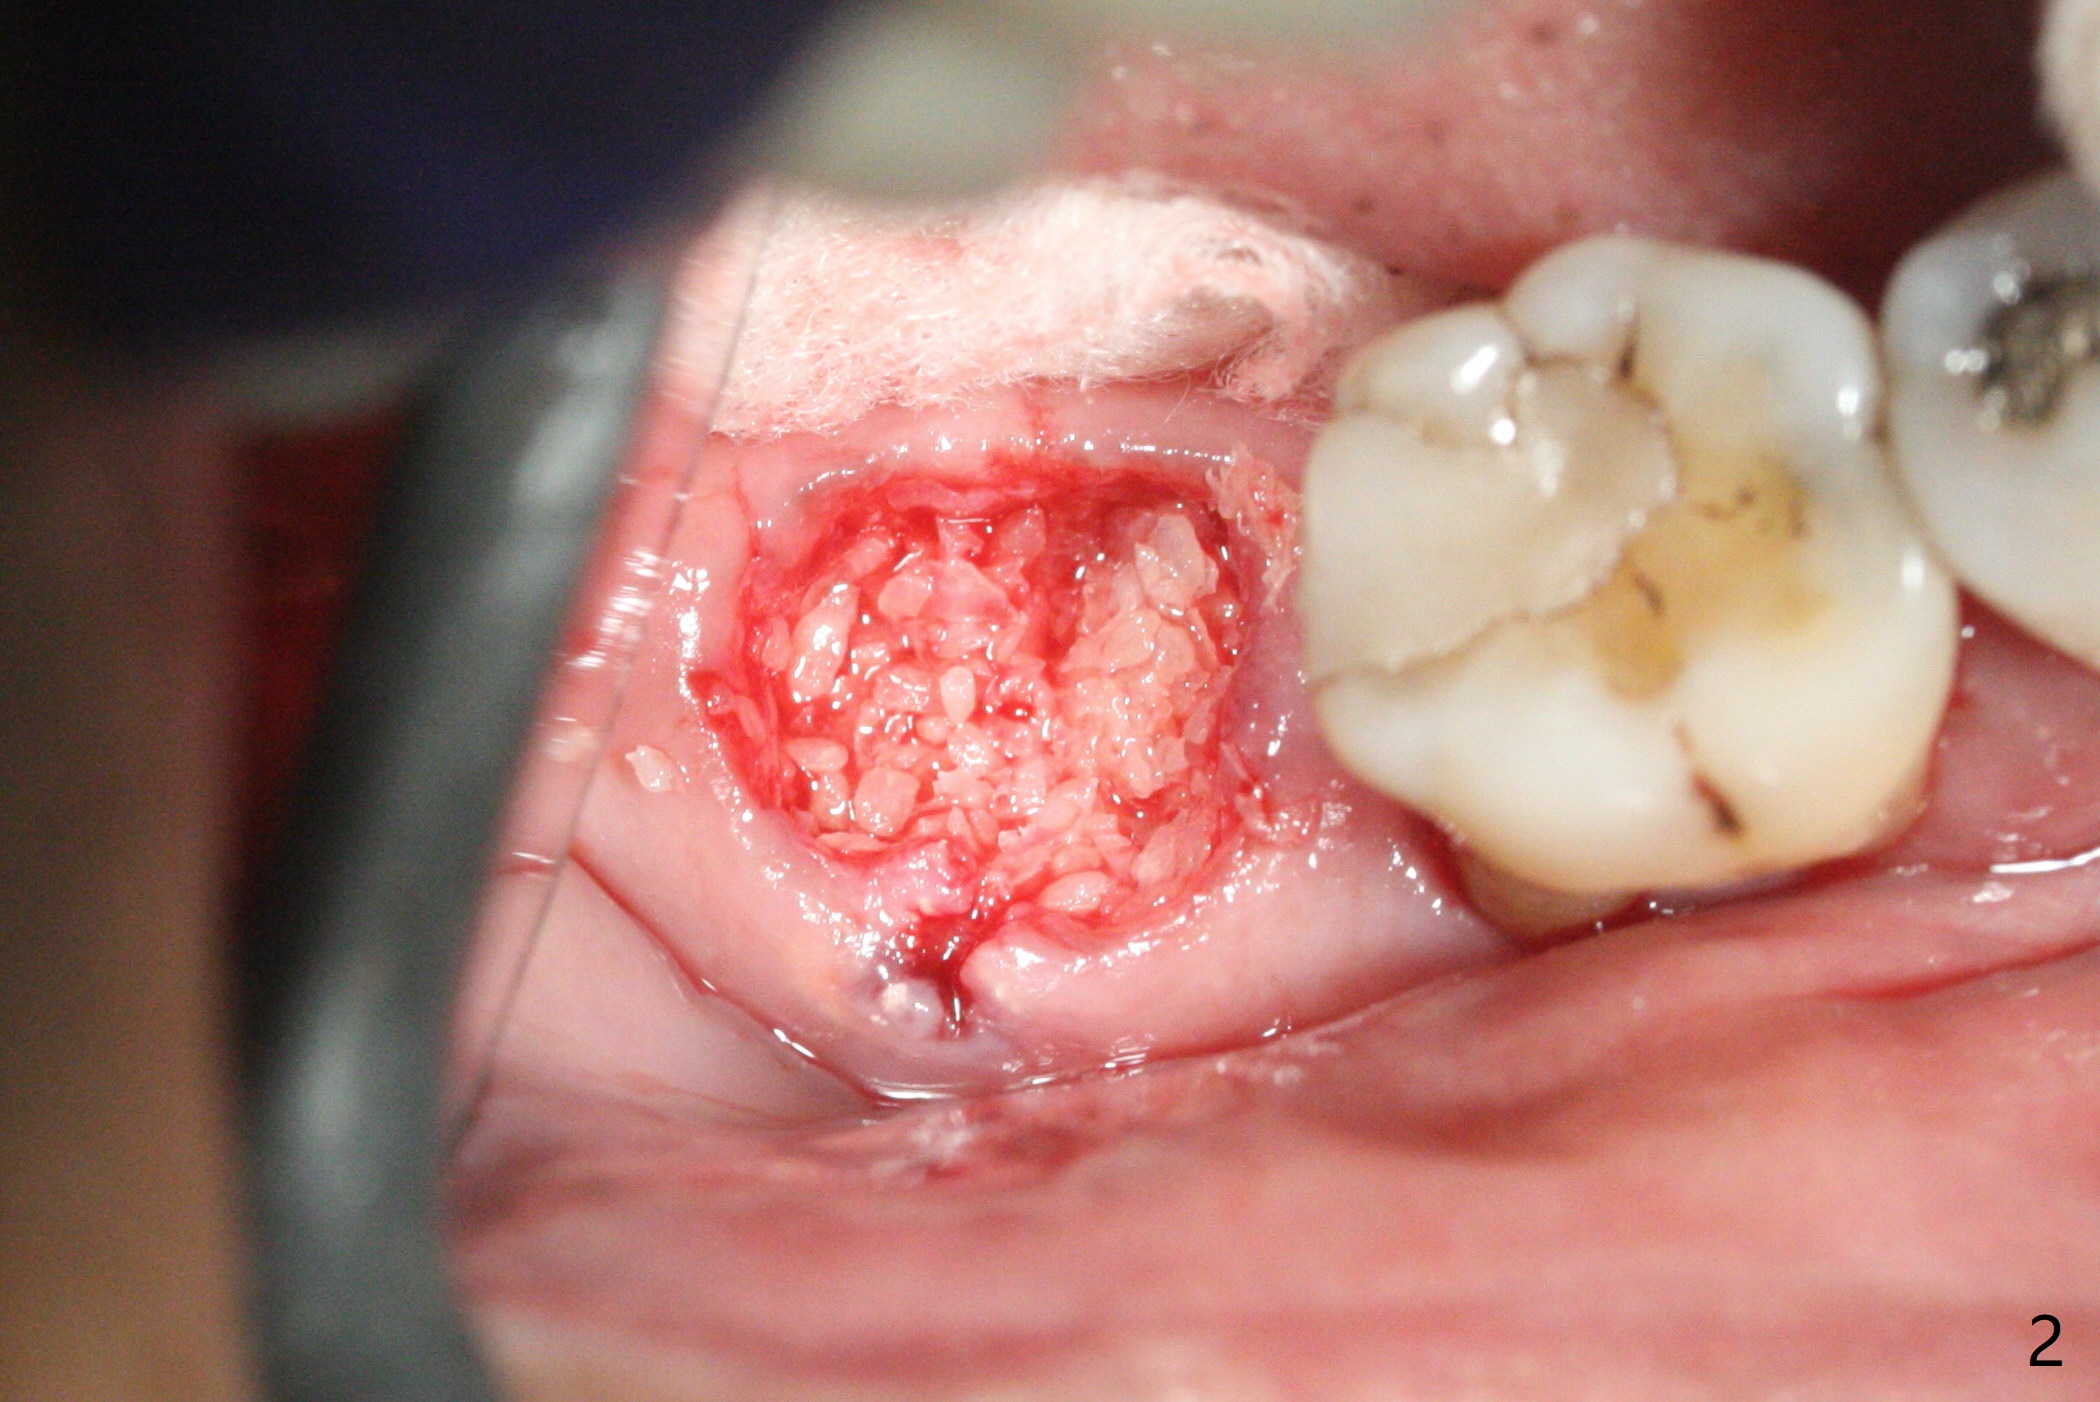

After extraction of the tooth #31 with mesial root fracture and a buccal fistula (Fig.1 <) and debride-ment, cortical: cancellous (50: 50) mineralized allograft (.5-1 mm) saturated with ~ .3 ml of .3 mg/ml of rhPDGF-BB (one component of GEM21S) is placed in the socket. Amazingly bone graft granules seem to stick to each other (semi sticky bone (Fig.2), as compared to PRF). The socket opening is covered with a piece of Osteogen plug and 12x12 mm Amnion-Chorion Allograft, followed by 4-0 PGA suture (Fig.3). The bone graft is packed as apical (Fig.4) and buccal (Fig.5 B) as possible. The patient will return to soft tissue healing check in a week. CT will be taken to determine whether the buccal plate is repaired 4 months postop. Watch Video. In fact COVIT 19 delays her return. The buccal plate seems to have reformed 7 months postop (Fig.6 >). The width and height of the ridge remains basically the same (compare Fig.7 and 8).